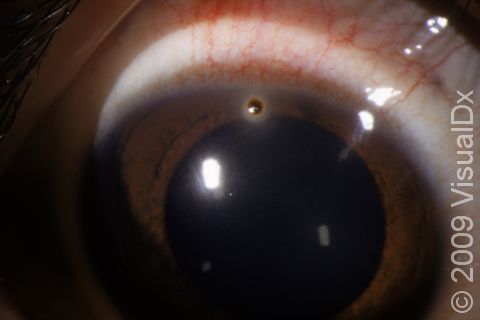

It is usually obvious when a foreign object is embedded in the skin. Large foreign bodies in the eye can be seen easily, but smaller objects may only be seen upon eye exam.

In the case of a foreign object in the eye, special instruments are required to examine the eye completely.